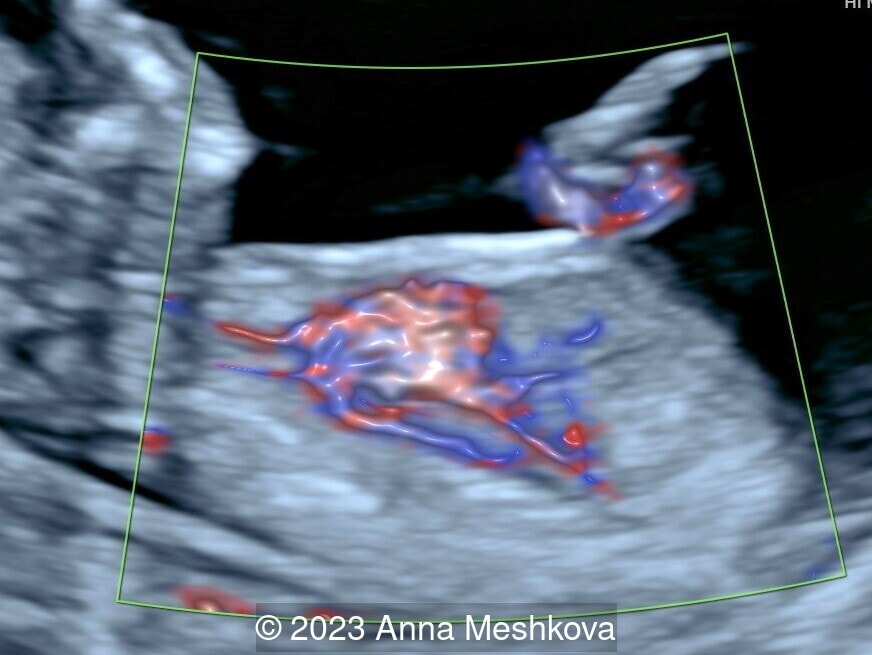

We present a case of D-transposition of the great arteries with ventricular septal defect diagnosed in early pregnancy.

• 3 vessel view demonstrating that the aorta arises from the right ventricle (Video 1,2)

• Sagittal plane through aortic arch shows parallel course of the great vessels (Image 2, Video 6,7)

Ao: Aorta; PA: Pulmonary artery; RV: Right ventricle

Image 6 Ao: Aorta; PA: Pulmonary artery; RV: Right ventricle